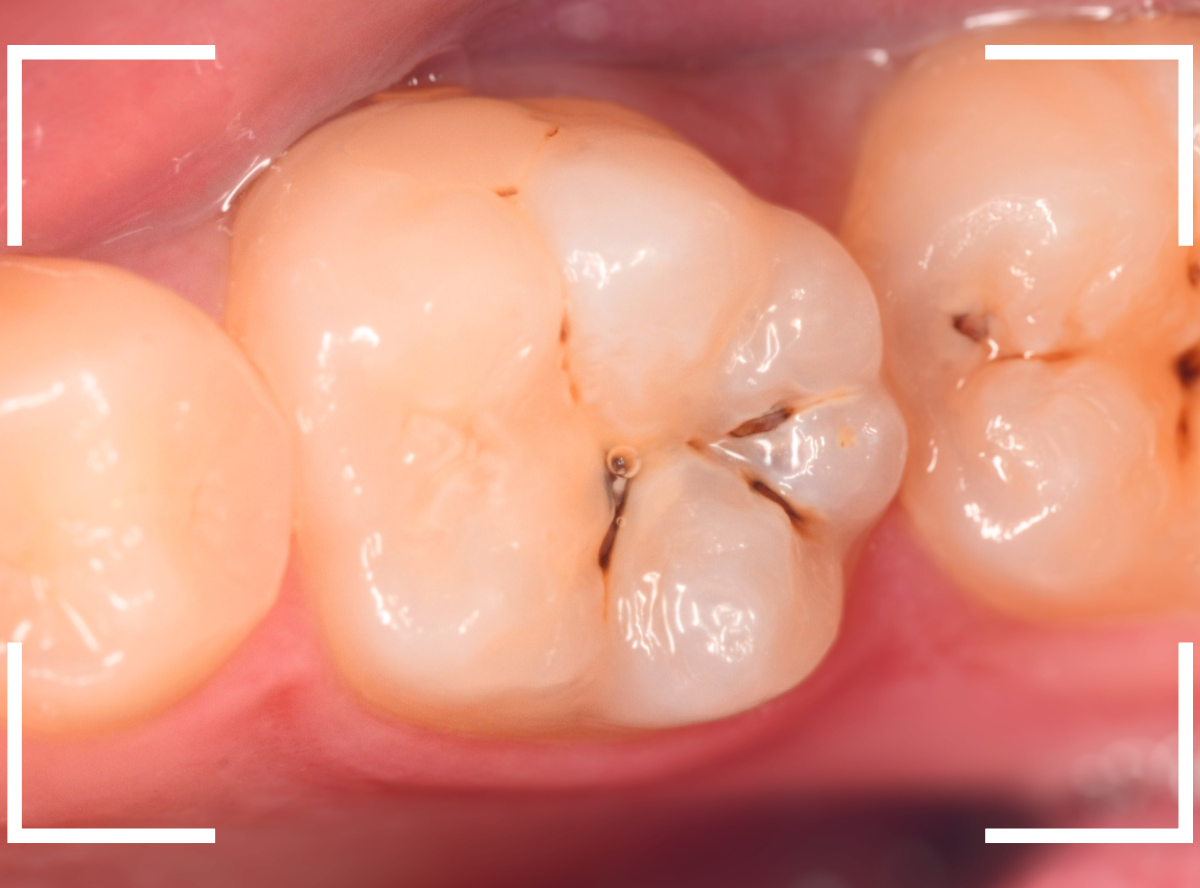

歯を上から確認すると、溝の周りが虫歯がありそうです。

写真では、2本の歯とも、歯の溝に虫歯が出来ているのが確認できます。

小窩裂溝部分に、小さな虫歯が確認できます。